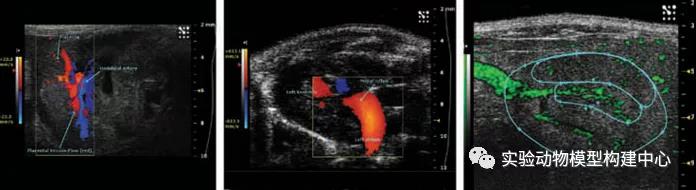

Vevo® 2100 超声成像系统

活体成像作为一种技术手段在生物医学特别是转化医学中具有重要的功能并得到越来越广泛的应用。Vevo® 2100 成像系统是第一个带有线性阵列技术和彩色多普勒功能的高频率、高分辨率数字成像平台。Vevo® 2100 成像系统集多项技术突破于一身,其中最突出的是用于小动物成像技术的高频线性阵列技术的开发。

•彩色多普勒显示血流方向,平均速度,确定B型超声无法看到的小血管